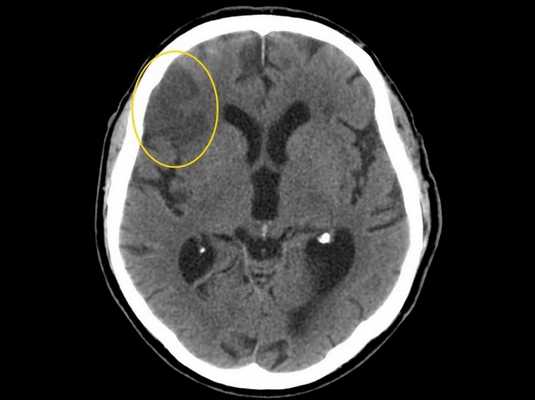

Ишемический инсульт головного мозга (зона поражения выделена желтым) на снимке КТ